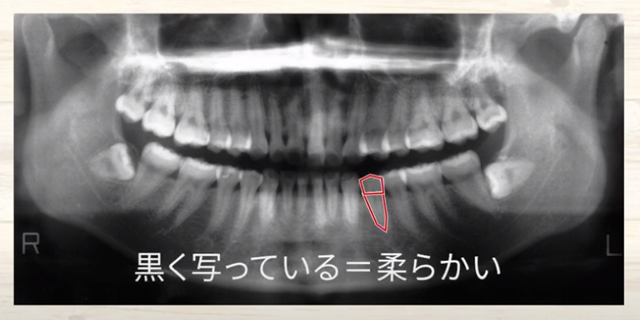

ですから、

硬い歯の頭があって

歯の根っこがあって、

ここの歯だと黒く写ってますね

そこは柔らかい

だから、歯の神経が生きているのではないかと考えます。